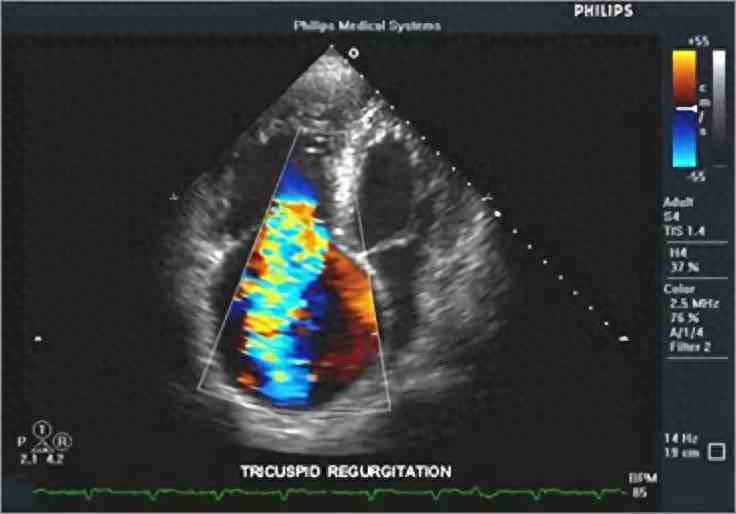

D型:是专门用来检测血液流动和器官活动的一种超声诊断方法,又称为多普勒超声诊断法。可确定血管是否通畅、管腔有否狭窄、闭塞以及病变部位。

D型--彩色多普勒超声诊断仪

D型超声诊断法即多普勒法 图 心脏彩超

新一代的D型超声波还能定量地测定管腔内血液的流量。近几年来科学家又发展了彩色编码多普勒系统,可在超声心动图解剖标志的指示下,以不同颜色显示血流的方向,色泽的深浅代表血流的流速。现在还有立体超声显象、超声CT、超声内窥镜等超声技术不断涌现出来,并且还可以与其他检查仪器结合使用,使疾病的诊断准确率大大提高。超声波技术正在医学界发挥着巨大的作用,随着科学的进步,它将更加完善,将更好地造福于人类。